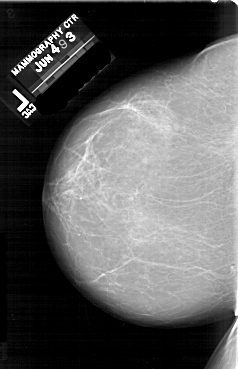

A_1640_1.RIGHT_MLO

RIGHT_MLO LINES 5761 PIXELS_PER_LINE 3166 BITS_PER_PIXEL 12 RESOLUTION 43.5 OVERLAY